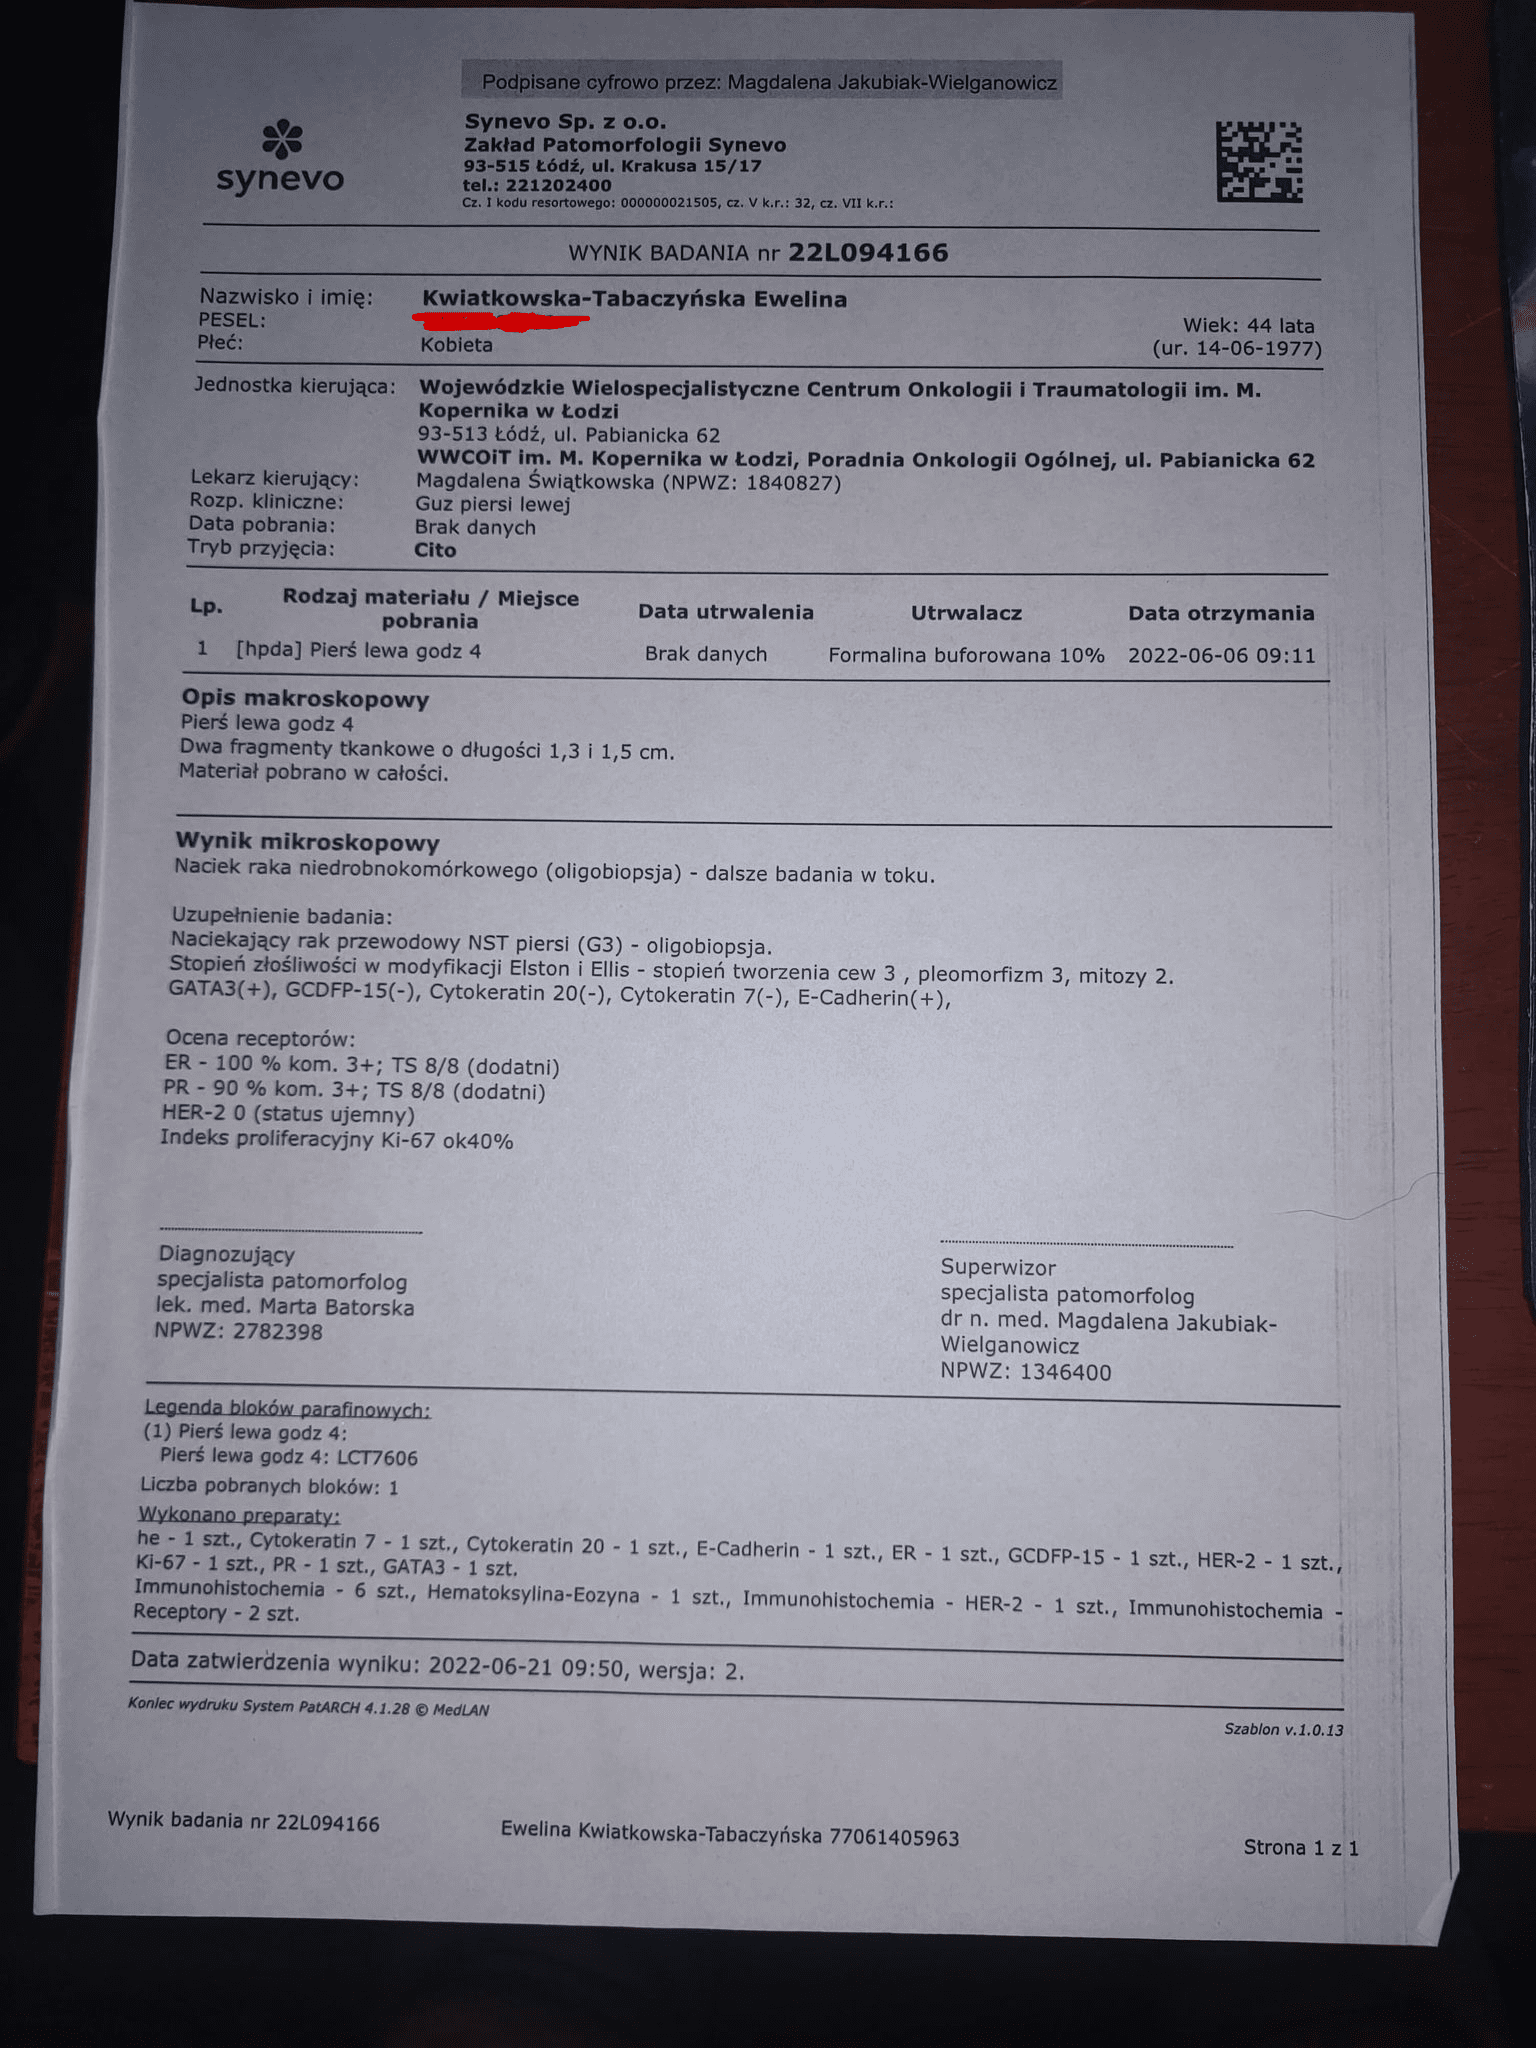

Złośliwy nowotwór piersi, po kolejnych badaniach stwierdzono przerzuty do kości.